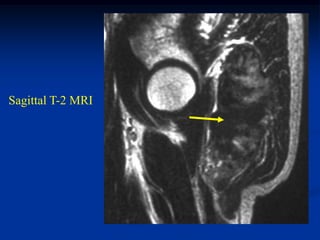

Case #250.3      Sag T-2                 Sag Gad

15 year female with painful enlarging desmoid past 6 months

while on chemotherapy

Axial T-2

vessels